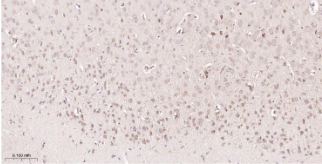

Immunohistochemical analysis of paraffin embedded Rat brain tissue slide using IHC0515R (Rat STAT6 Kit).